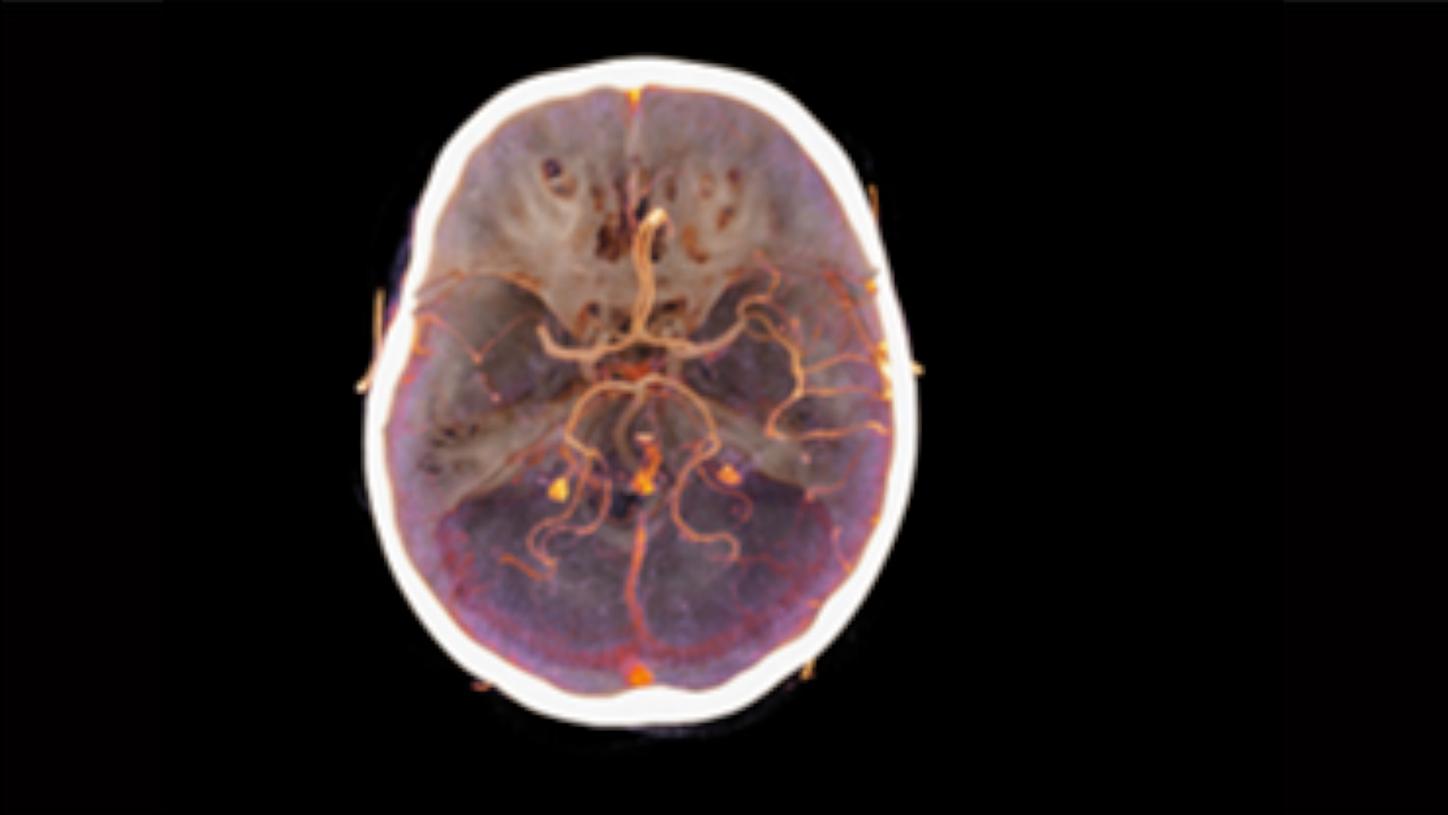

Rai AT, et al., J Neurointervent Surg (9) 2017